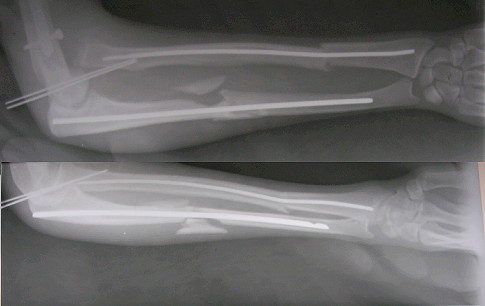

Dear All, Another case being put up on behalf of my colleague20 yrs old active male. RTA 7 weeks ago. Closed # both bones forearm with anterior dislocation of the radial head, closed # midshaft humerus same side, crush injury left lower limb beyond salvage.

At the place of first management, the radius and ulna were fixed intramedullary by closed method, some reduction of the radial head achieved and an attempt made to keep the radial head in position. BK amputation was done. Three days later, he shifted to another hospital where the humerus was fixed with a locked nail and findind the radial head remaining dispalced anteriorly an attempt was made to reduce the radial head closed.(without success). Now the patient has the radial head still displaced anteriorly. There is no radial palsy. My suggestion was as follows:The reason for the head not getting reduced is at least partially due the length of ulna not having been restored.ExFix of any type in the ulna, distract till the legth is restored and try to reduce by flexing the elbow to extreme flexion. If necessary open reduction of the radial head and retain with a sling made of fascia lata.Your comments are welcome. RegardsV M Iyer. Iyer Orthopaedic Centre, 103,Railway lines Solapur India

Not likely to my view. The problem goes from 1)the annular ligament rupture and 2)the wires missed the radial head - they are not even bent while the head is out of its position after the "fixation".

There is a well established Ilizarov technique for forearm fractures and particularly the Monteggia conponent - after closed reduction the proximal radius is fixed by an olive wire, it is a single wire through the both bones.